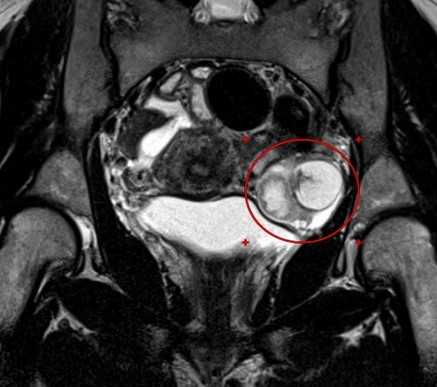

МРТ малого таза. В структуре яичника отмечается крупная киста с толстыми стенками, с неоднородным (белковым) содержимым, без перегородок и папиллярных разрастаний.

Отмечается повышение интенсивности МР-сигнала от содержимого кисты на ДВИ с признаками выраженного снижения на ИКД (в,г) - МР-признаки воспалительного (гнойного) содержимого.